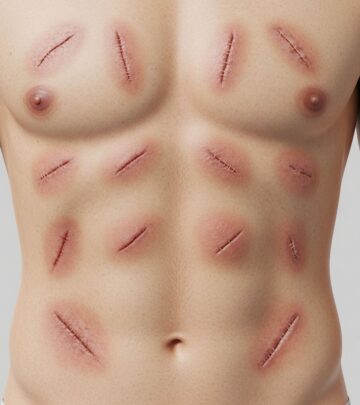

Portal hypertension occurs when blood pressure in the portal vein—the vessel that carries blood from the digestive organs to the liver—becomes abnormally elevated. This condition typically develops as a result of liver cirrhosis, chronic hepatitis, or other liver diseases that obstruct normal blood flow. The elevated pressure can lead to serious complications including the formation of enlarged veins (varices) in the esophagus and stomach, which carry a significant risk of life-threatening bleeding.